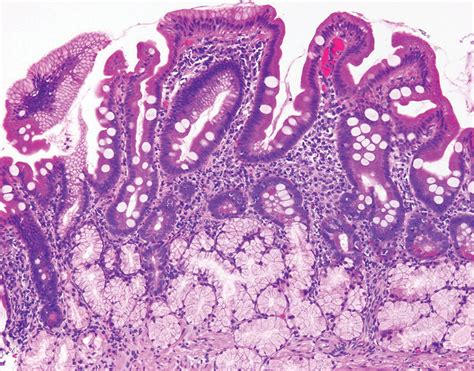

Biopsy The definitive way to affirm if a increment is cancerous by analyzing a tissue sampling.